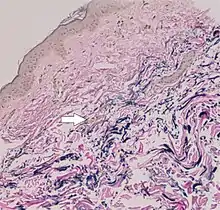

In PXE, there is mineralization (accumulation of calcium and other minerals) and fragmentation of the elastin-containing fibers in connective tissue, but primarily in the midlaminar layer of the dermis, Bruch's membrane and the midsized arteries.[26] Recent studies have confirmed that PXE is a metabolic disease, and that its features arise because metabolites of vitamin K cannot reach peripheral tissues.[27] Low levels of PPi cause mineralization in peripheral tissues.[19]

The diagnostic criteria for PXE are the typical skin biopsy appearance and the presence of angioid streaks in the retina. Criteria were established by consensus of clinicians and researchers at the 2010 biennial research meeting of the PXE Research Consortium.[29] and confirmed at the 2014 meeting[30] These consensus criteria state that definitive PXE is characterized by two pathogenic mutations in the ABCC6 or ocular findings – angioid streaks > 1 DD or peau d’orange in an individual <20 years of age together with skin findings:

- Diagnostic histopathological changes in lesional skin: Calcified elastic fibers in the mid and lower dermis, confirmed by positive calcium stain

| Pseudoxanthoma elasticum | LM: Mid-dermal calcification and fragmentation of elastic fibers EM: Mineralization in elastic fiber core |

| PXE-like disease with coagulation deficiency | LM: Middermal calcification and fragmentation of elastic fibers EM: Mineralization in elastic fiber periphery |